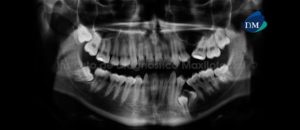

Paciente femenino de 34 años es referido al Instituto de Diagnóstico Maxilofacial para seguimiento de lesión en mandíbula. Se muestra la radiografía panorámica inicial (Figura